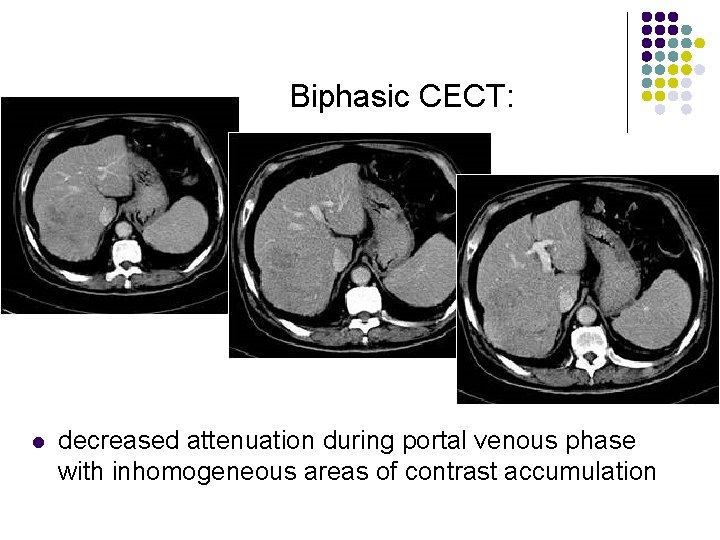

Biphasic CECT: l l l enhancement during hepatic arterial phase (80%) decreased attenuation during portal venous phase with inhomogeneous areas of contrast accumulation isodensity on delayed scans (10%) thin contrast-enhancing capsule (50%) due to rapid washout wedge-shaped areas of decreased attenuation (segmental/lobar perfusion defects due portal vein occlusion by tumor thrombus)

Biphasic CECT: l decreased attenuation during portal venous phase with inhomogeneous areas of contrast accumulation

Biphasic CECT: l decreased attenuation during portal venous phase with inhomogeneous areas of contrast accumulation